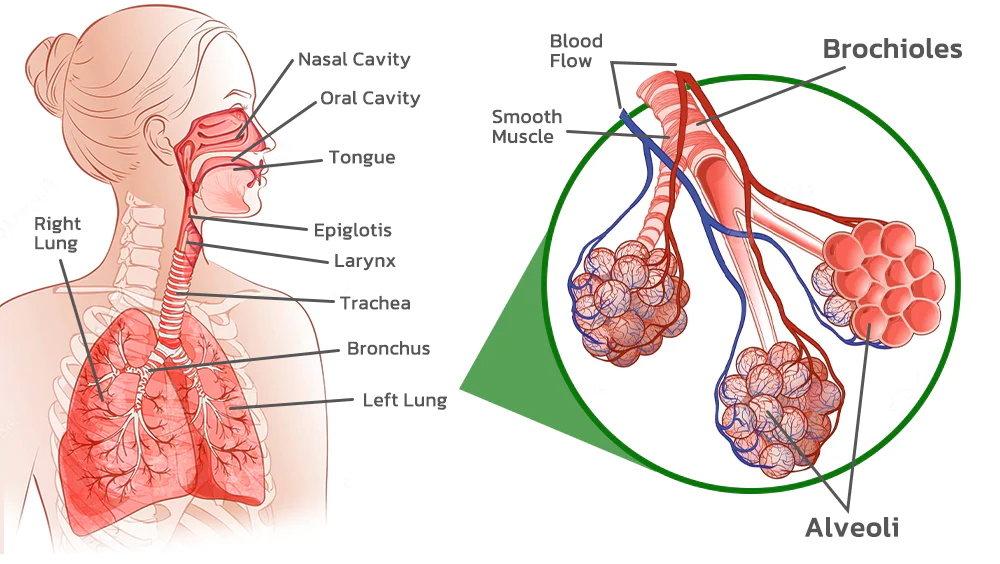

FastClean Cleaning Lung Herbal Extracts Ring is an inhaler that is used by inhaling through the nose. The herbal extracts are then absorbed through the trachea and into the lungs. The active ingredients work to dilute the mucus in the trachea and lungs, making it easier to expel phlegm and other waste materials from the respiratory system. This process helps to cleanse the lungs and upper airways and can lead to improved respiratory function and overall health.